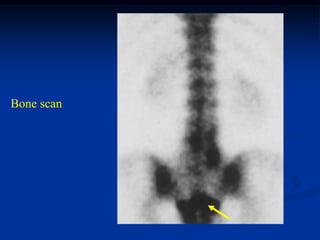

Bone scan

Low power photomic with osteofibrous dysplasia